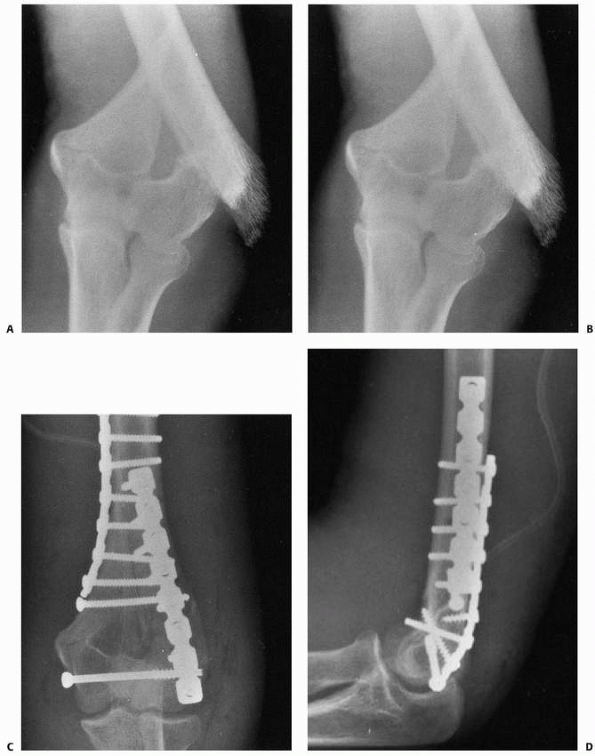

![]() |

FIGURE 15-27 A,B. Fracture of the capitellum in a 14-year-old boy. C,D. After open reduction and fixation with two small cannulated screws through a lateral approach.

|

if an anatomic reduction can be achieved with a minimum of open

manipulation or dissection, then we prefer to reattach it with two

small cannulated screws inserted from posterior to anterior through a

lateral approach. Enough bone must be present in the capitellar

fragment to engage the screw threads, and if possible, countersink the

heads of the screws (see Fig. 15-27). If the